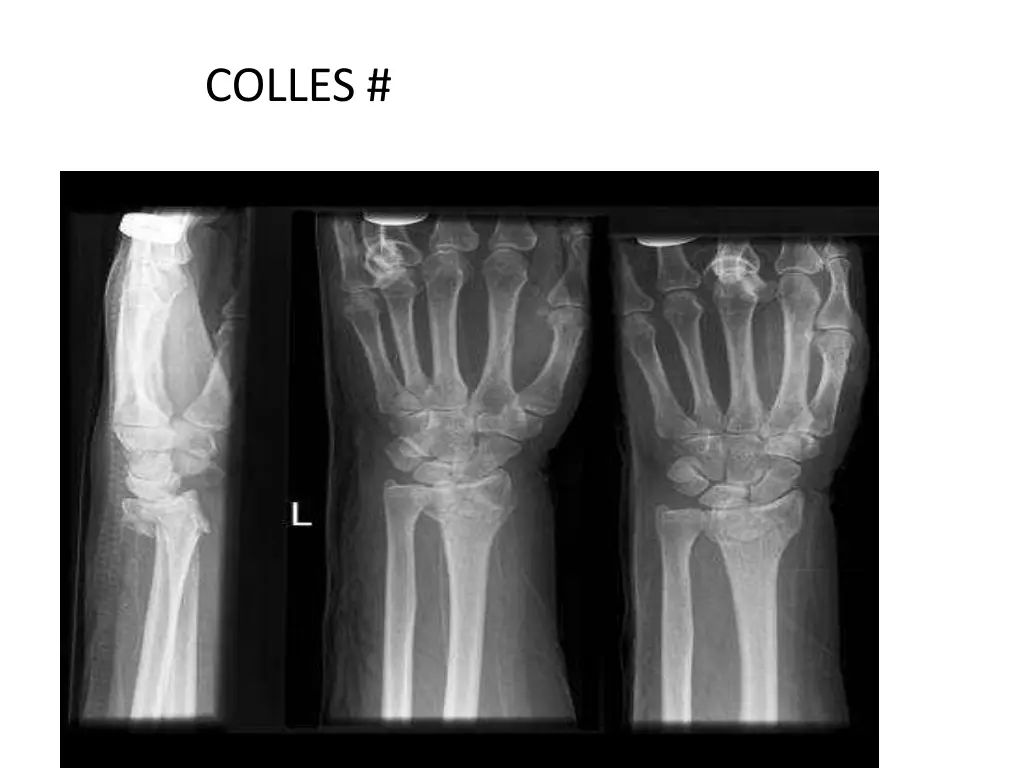

5. ORTHOPAEDIC CONDITIONS IN INPATIENTS UPPER LIMB SUPRA CONDYLAR # HUMERUS BOTH BONE # FORE ARM COLLES #

7. COLLES #